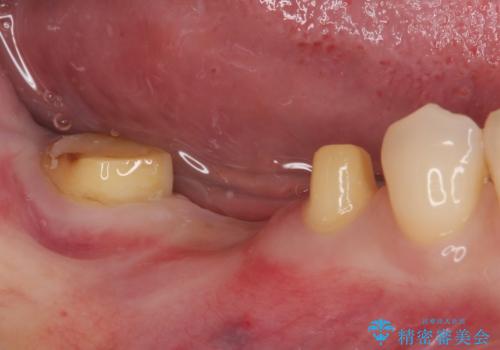

再度の歯を根管治療したため、抜歯した部位の補綴治療は、強度の問題からブリッジよりもインプラントをおすすめしましたが、患者様希望によりブリッジを選択しました。

一番奥の歯は歯肉から露出している高さが少なく、クラウンを装着する不十分であったため、歯冠長延長術を行うこととしました。

根管治療を行った奥歯をブリッジの支台歯としているため、咬合力による負担を軽減するために、就寝時にマウスピースを装着するように指導しています。